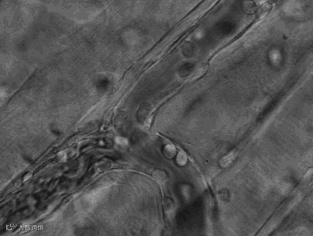

T 细胞正在识别、灭杀突变的癌细胞